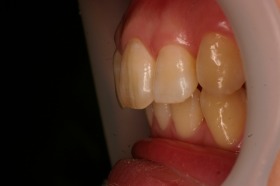

ご覧の症例は出っ歯を矯正治療でキレイにしたケースです。

よく出っ歯は日本人に多いようなイメージがありますが

、世界的に見ても受け口と比較して出っ歯は多いようです。

このような場合では歯を抜いて矯正するか

、抜かずに矯正するか分かれるケースです。